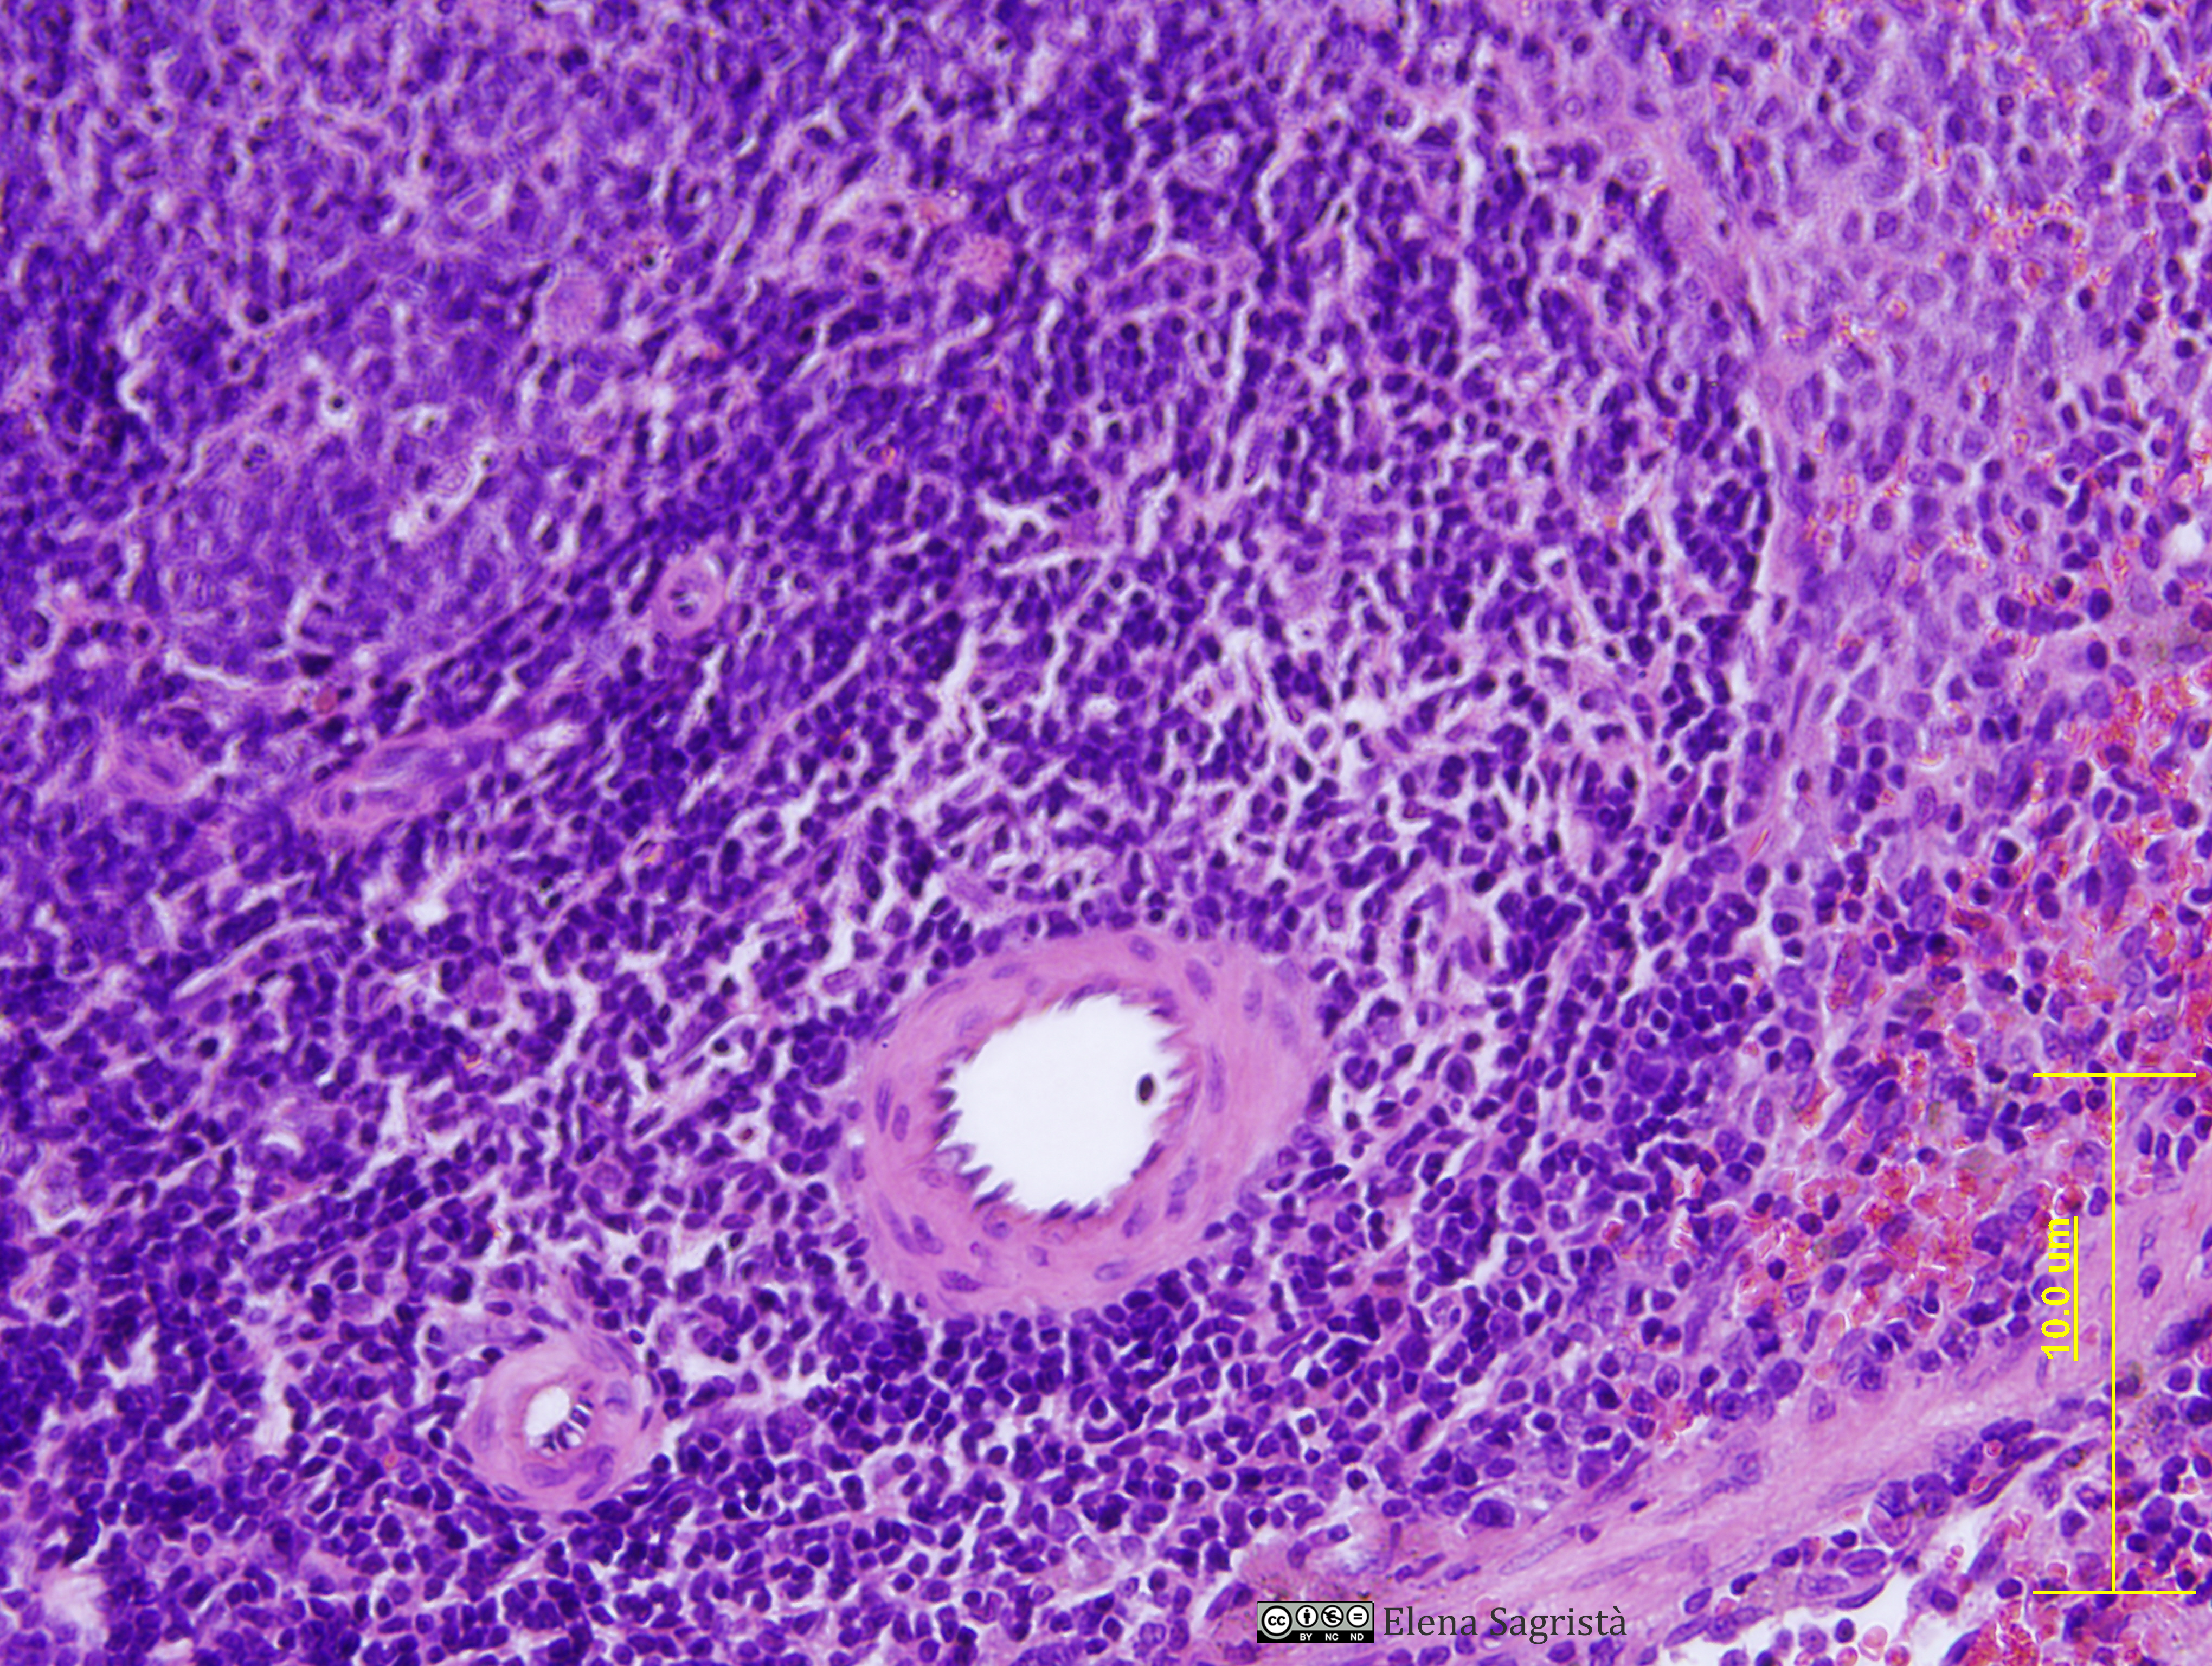

Histologia imatges: 10 Vasos sanguinis i limfàtics

Imatges de preparacions histològiques de Vasos sanguinis i limfàtics. Microscopia òptica.